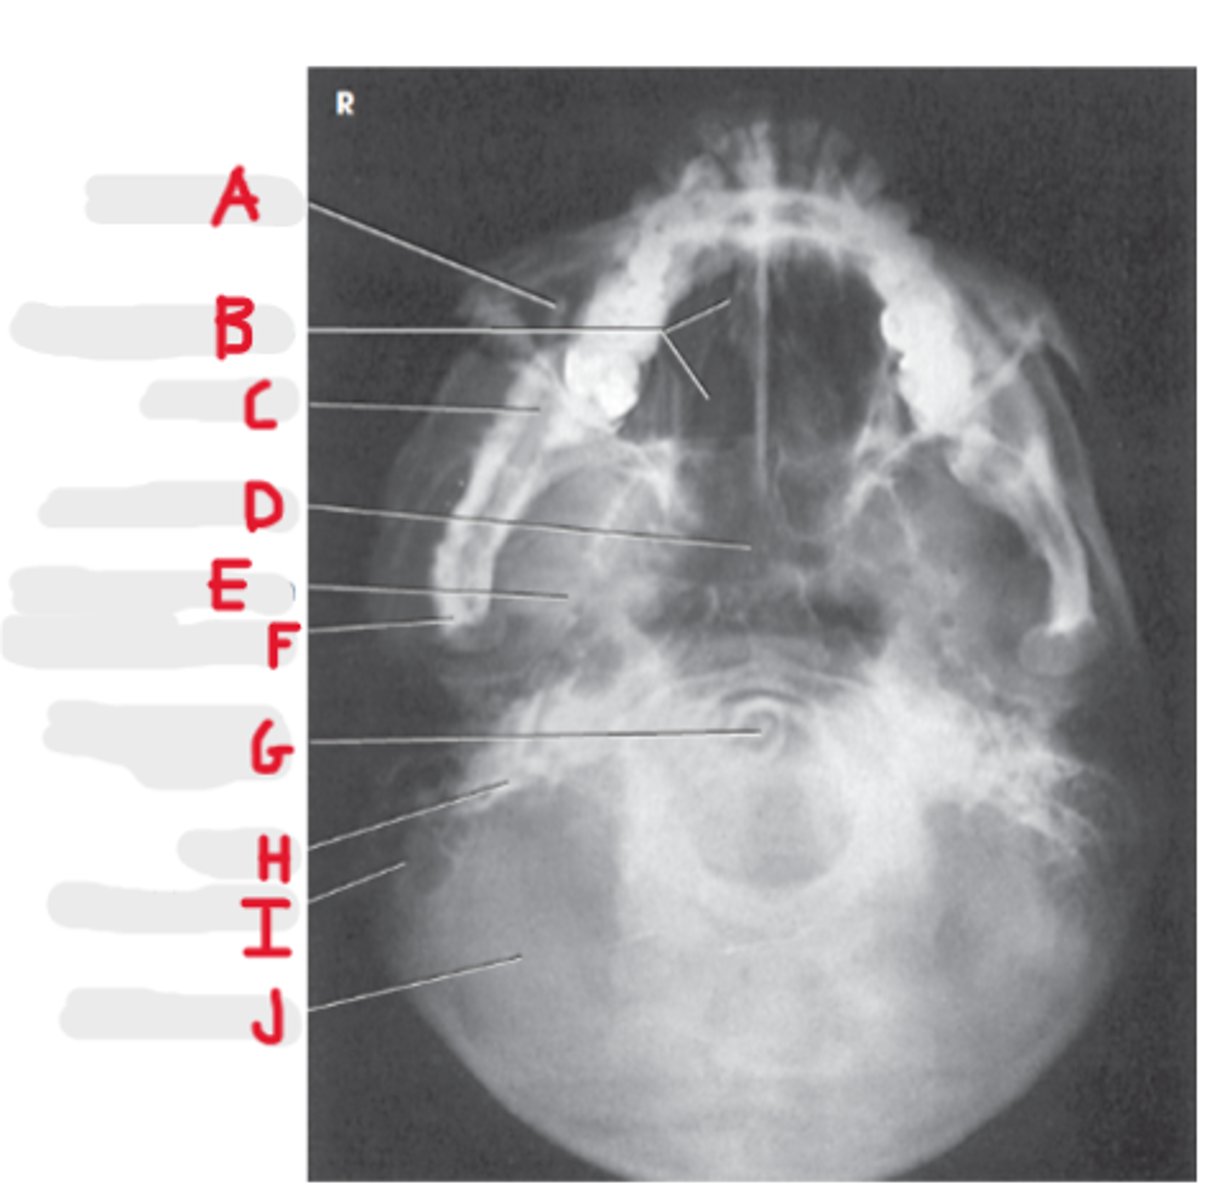

Submentovertex (or vertical) SMV

What projection is this?

CR - perpendicular to IOML

enters 1-1 1/2 inch below the mentum

What is the CR for the SMV?

Infraorbital meatal line (IOML)

What line is parallel to the IR for the SMV?

Basal view because it demonstrates the base of the skull

What is the SMV known as and why?

Sphenoid and ethmoid

What sinuses are best demonstrated on an SMV?

Look for equidistant lateral border of skull to mandibular condyles

How do we look for rotation/tilt on an SMV radiograph?

Maxillary sinus

A

Upper teeth

B

Sphenoid sinuses

C

Lower teeth

D